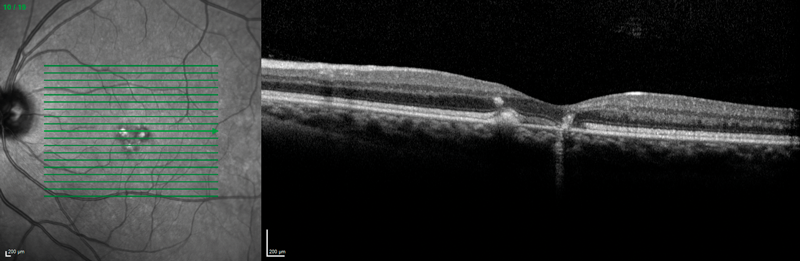

Figure 1: Optical coherence tomography showing right (a) < left (b) macular defects at the level of

the retinal pigment epithelium and above, and additional right intraretinal hyperreflectivity (a).

On the slit-lamp we saw macular dystrophies more to the left than the right eye, which seemed to be located at the level of the retinal pigment epithelium (RPE) and above as the optical coherence tomography (OCT) scans revealed (Figure 1). In addition, the right eye showed some unusual findings with intraretinal hyperreflectivity in the OCT scan, and increased background fluorescence in the angiography (Figure 2). The left, by contrast, demonstrated early hyperfluorescence during the angiography (Figure 2).